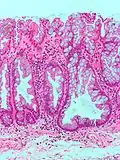

• Villous adenomas are commonly found in the rectal area and they are normally larger in size than the other two types of adenomas. They tend to be non-pedunculated, velvety, or cauliflower-like in appearance and they are associated with the highest morbidity and mortality rates of all polyps. They can cause hypersecretory syndromes characterized by hypokalemia and profuse mucous discharge, and can harbor carcinoma in situ or invasive carcinoma more frequently than other adenomas.